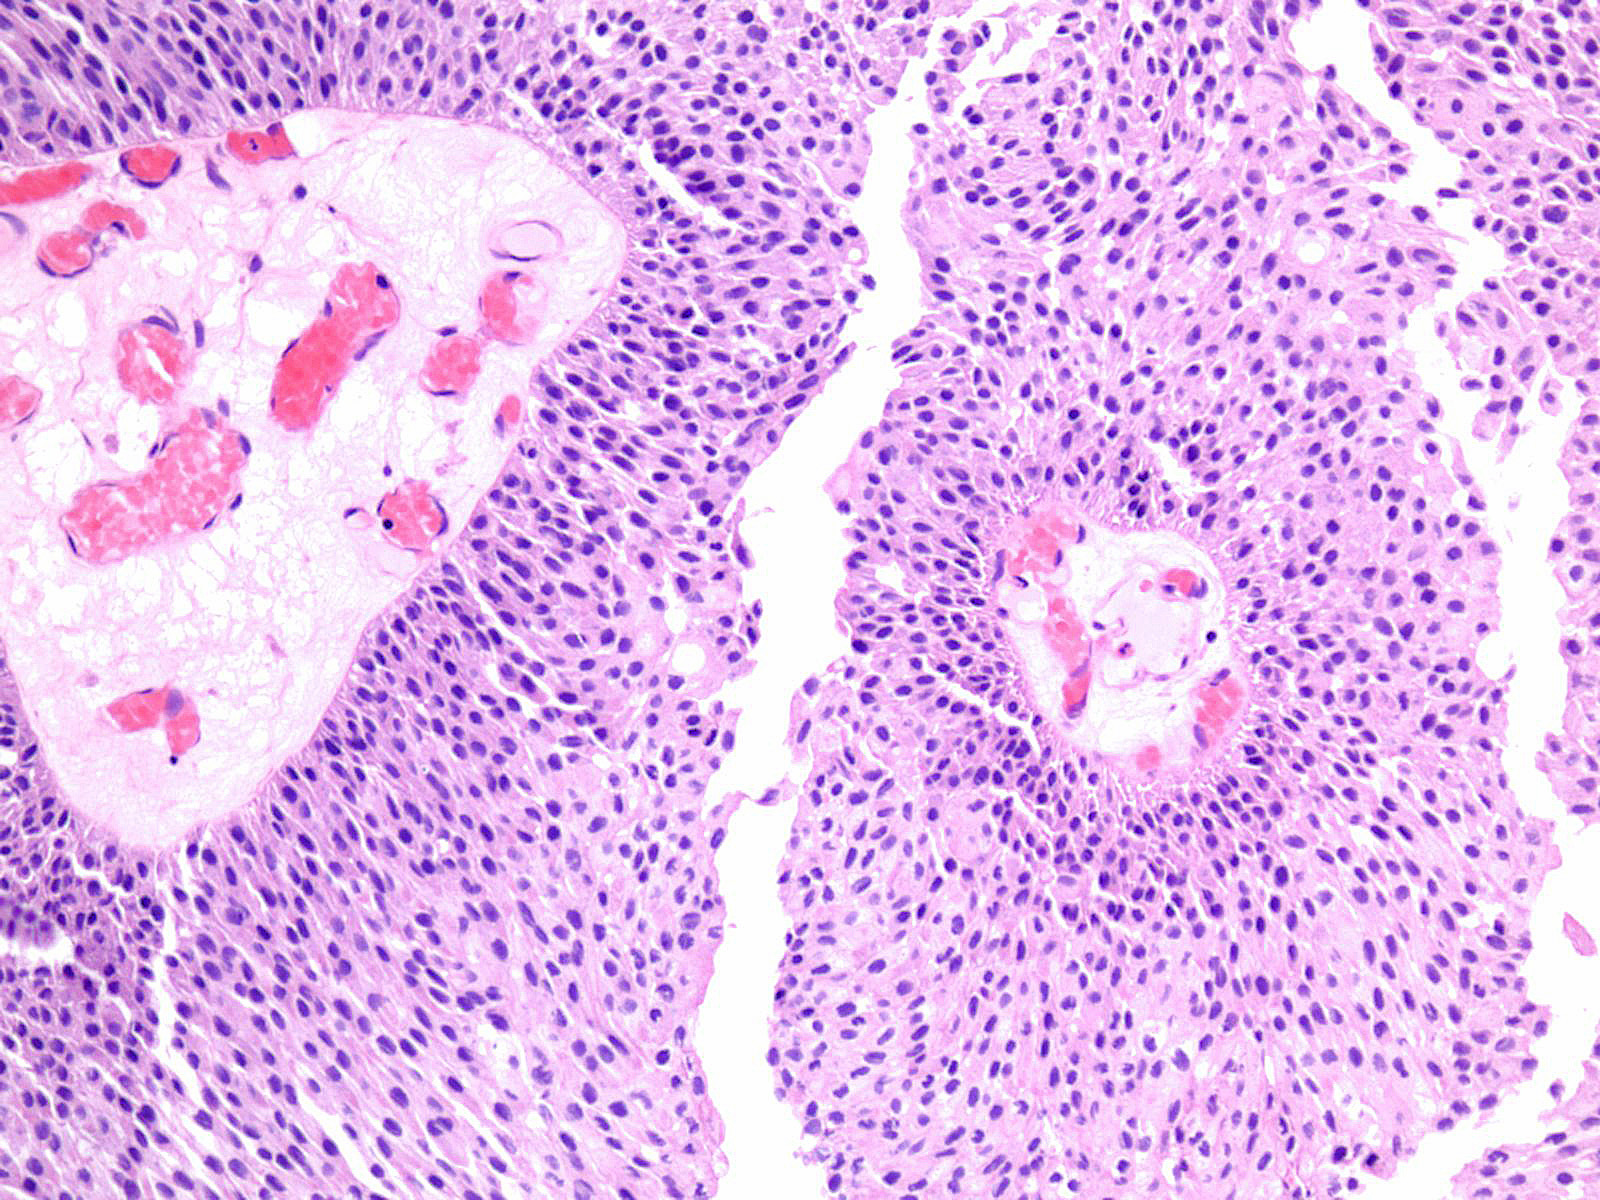

Consensus grade: Low-grade papillary urothelial carcinoma (LG-PUC)

Lesion shows moderate variation in nuclear size, shape and chromatin. Scattered nuclei are significantly enlarged and hyperchromatic relative to other nuclei. Lesion still maintains an overall orderly appearance.